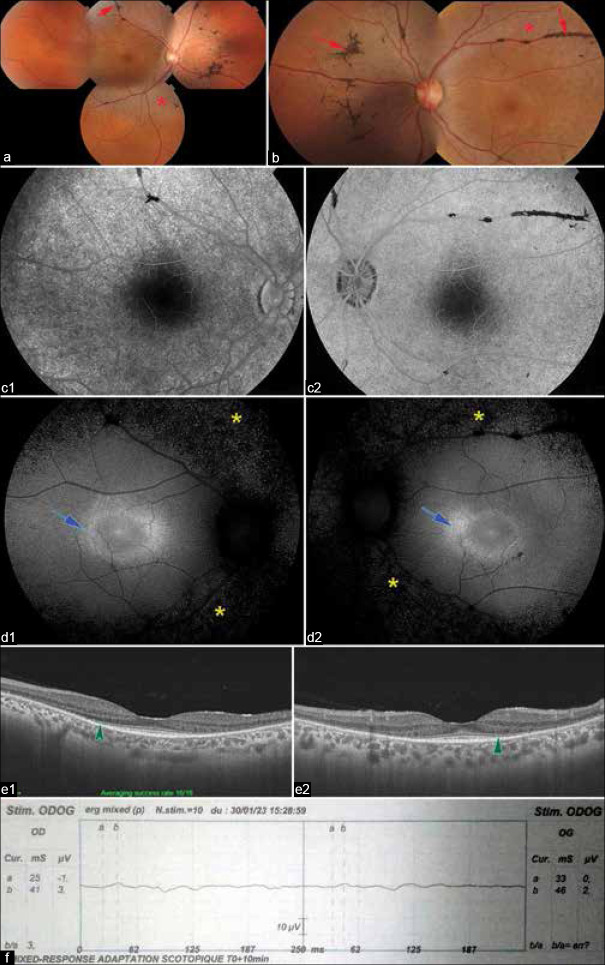

Purpose: To report the atypical case of a patient with mucopolysaccharidosis type II (MPS II) in whom bilateral pigmented paravenous chorioretinal atrophy (PPRCA) was found.

Results: We present the case of a 31-year-old male patient who presented with decreased visual acuity and in whom fundus examination and multimodal imaging revealed a typical appearance of bilateral symmetrical PPRCA. Our patient also had thick facies with hypertelorism and stubby hands, which prompted an enzyme assay revealing MPS II.

Conclusions: PPRCA is an uncommon condition with an uncertain origin that continues to be a subject of debate. Our case represents an unusual association that points to a potential genetic origin; however, further studies are needed to understand this condition.